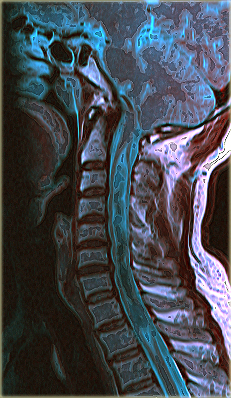

Томография органов и мягких тканей шеи, МРТ или КТОсмотр шеи путём томографии включает обследование паращитовидной и щитовидной железы,  верхних дыхательных путей, верхней части пищевода, слюнных желез, сосудов, костей.

Рентгеновские лучи, применяемые в КТ, отменно отображают плотные образования и полые органы. С помощью электромагнитного излучения лучше дифференцируются мягкие ткани в области горла. Поэтому КТ рекомендовано для осмотра шейных позвонков, а МРТ при повреждениях связок и мышц шеи.

Снимки шейного отдела позвоночника, полученные с помощью компьютерного томографа, очень качественные, благодаря чему диагносты легко определяют патологические изменения, их разновидности, стадии развития. Но  послойные изображения внутренних органов горла выражены слабее. Это связано со свойствами рентгеновских лучей, визуализирующих лучше плотные структуры тканей.

Строение мягких тканей врачам удаётся изучить тщательнее по снимкам, полученным за счет ядерно-магнитного резонанса. Внутренние органы в шейной области имеют на снимках ровные, чёткие границы. Поэтому при опухолях в гортани, заболеваниях лимфатических узлов, аномальном строении сосудов шеи рекомендовано проводить МРТ. Подобные изменения обнаруживаются и путём КТ при введении контрастных веществ, содержащих йод.